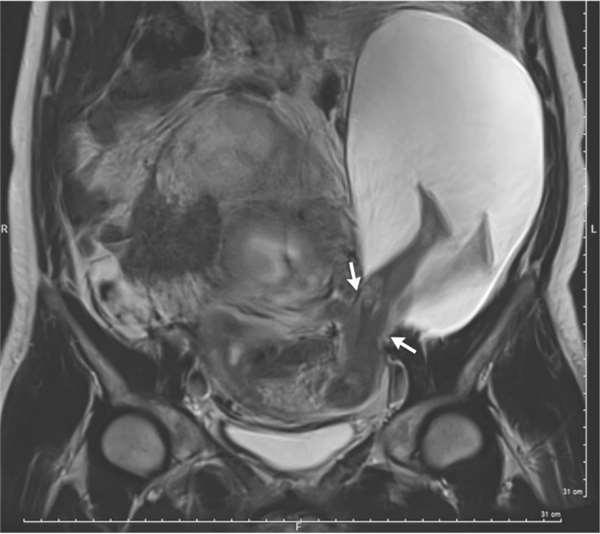

從這張核磁共振的影像中,可以看到這名生命力強烈的嬰兒,踹破母親的子宮,將腳伸出子宮外踢到其他器官,離奇的畫面就連醫生也被嚇壞了。

不久之前,當法國的婦產科醫生Pierre-Emmanuel Bouet替懷孕22週的孕婦產檢時,赫然發現到胎兒並沒有好好地待在子宮內生長,反而是兩腳伸直的穿出子宮外,罕見畫面讓醫生直呼:「從來沒看過!」就連醫學文獻上也僅有26起案例。

據悉,該名孕婦之所以會有這麼嚴重的子宮壁撕裂,起因在於先前的五次剖腹生產,雖然剖腹留下的疤痕會變厚,不過周圍的子宮壁會變得比以往脆弱,然而再懷孕後的壓力容易將子宮壁撐得更薄,於是在胎兒強勁的胎動後,往往會造成撕裂的狀況發生,所以沒有意外的,包著羊膜的寶寶的腳也就隨著滑出子宮的缺口。